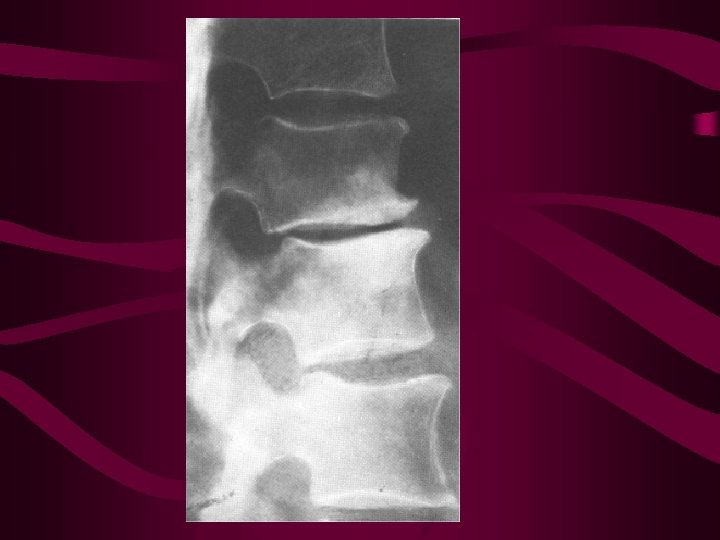

Lumbar Disc Degeneration Events • • • decreased proteoglycan content decreased hydrophilia decreased water content increased compressibility compromised stress dispersal randomized circumferential tearing (clefting) increased type 1 and decreased type 2 collagen content increased disc stiffness and decreased mobility increased height

Mechanism of Disc Height Increase • relative reduction in horizontal trabeculae • loss of lateral bracing of vertical trabeculae • collapse of vertical trabeculae in weight bearing area • increased concavity of the end plate • expansion of the disc into the increased • concavity